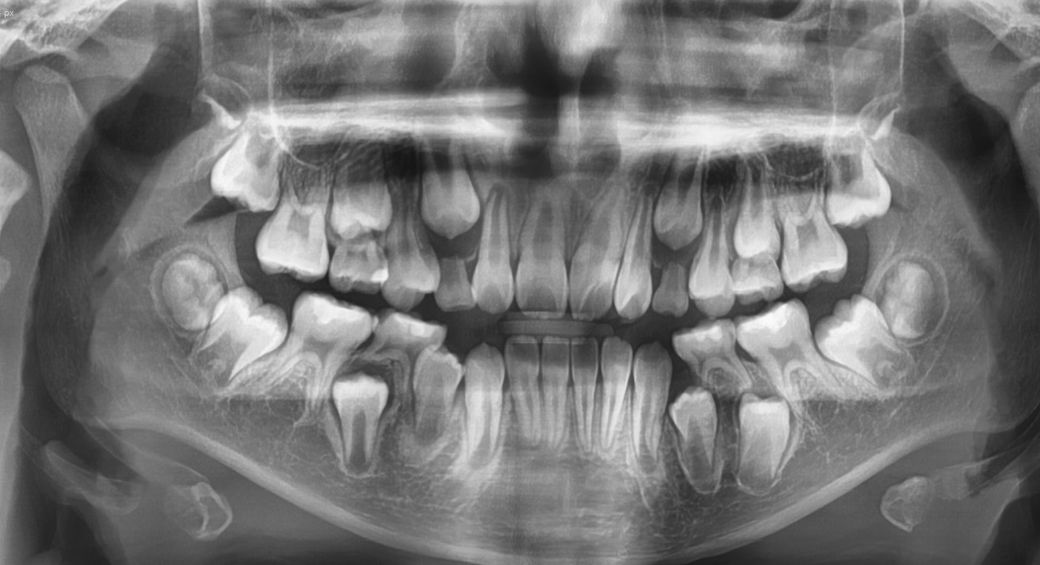

치아 올라올 공간이 부족해요~~ㅠㅠㅠ

아이 치아 올라올 공간이 부족하여

옆으로 나온 상태에요

나이는 10세 이구요~

사진으로 봤을 경우에는 유구치가 조기 상실되면서 공간이 부족하여 맹출경로가 어긋난것으로 보입니다.